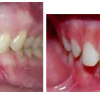

Ülemise hambakaare kitsenemine ehk tagumiste hammaste risthambumus

Hammustades on näha, et alumine hambakaar on laiem kui ülemine. Tagumine risthambumus võib olla kas mõlemapoolne või ühepoolne ja sageli hambakaarte keskjooned hammustades ei ühti. Tagumist risthambumust võib esineda 10...